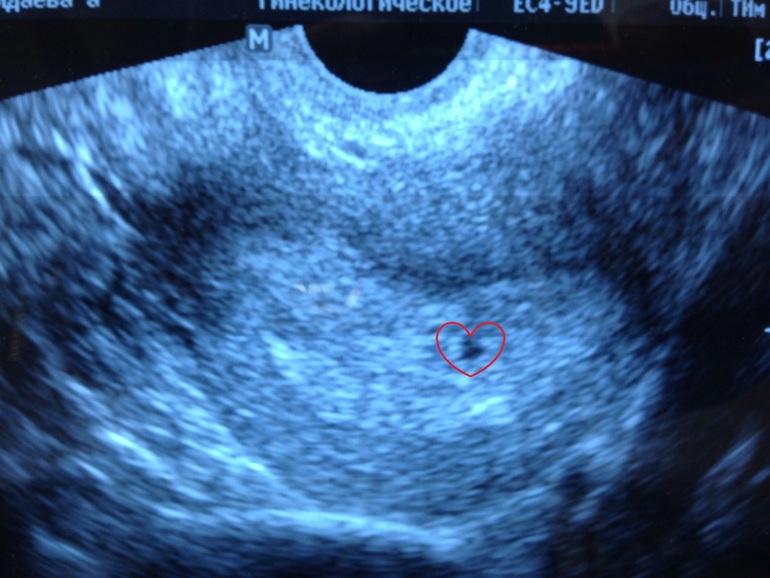

Вчера мы так же посетили врача,сделали узи и нашли нашу кнопку, мы еще совсем махонькие 3,3 мм, но мы уже с мужем как только можем укутываем любовью наше маленькое чудо)

Мы в правильном месте прикрепились, тонуса нет, проблем нет, сказали больше позитива и без нервов) Мы так и делаем, верим в самое лучшее и 14 февраля идем слушать сердечко нашей крохи

Знакомьтесь.. Наша будущая гордость